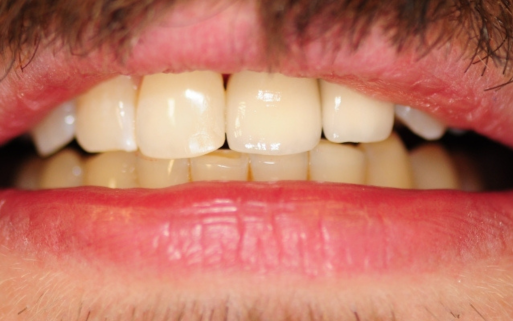

PRZED

PO

Przed i Po Naszych Klientów